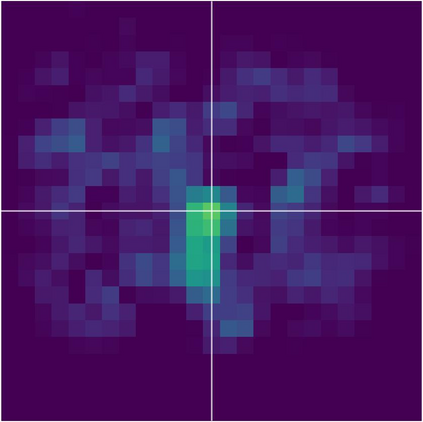

Various imaging modalities allow for time-dependent image reconstructions from measurements where its acquisition also has a time-dependent nature. Magnetic particle imaging (MPI) falls into this class of imaging modalities and it thus also provides a dynamic inverse problem. Without proper consideration of the dynamic behavior, motion artifacts in the reconstruction become an issue. More sophisticated methods need to be developed and applied to the reconstruction of the time-dependent sequences of images. In this context, we investigate the incorporation of motion priors in terms of certain flow-parameter-dependent PDEs in the reconstruction process of time-dependent 3D images in magnetic particle imaging. The present work comprises the method development for a general 3D+time setting for time-dependent linear forward operators, analytical investigation of necessary properties in the MPI forward operator, modeling aspects in dynamic MPI, and extensive numerical experiments on 3D+time imaging including simulated data as well as measurements from a rotation phantom and in-vivo data from a mouse.